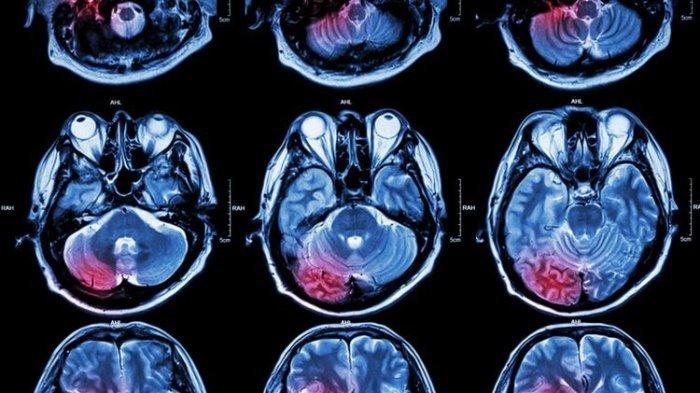

TRIBUNHEALTH.COM - Tumor otak adalah salah satu masalah yang masih menghantui dunia kesehatan yang menyebabkan tingkat kecacatan dan kematian yang memengaruhi kehidupan manusia dan memiliki angka kekambuhan yang tinggi akibat respon yang buruk terhadap pengobatan.

Tumor otak merupakan massa atau benjolan yang terjadi akibat pertumbuhan sel abnormal di dalam otak.